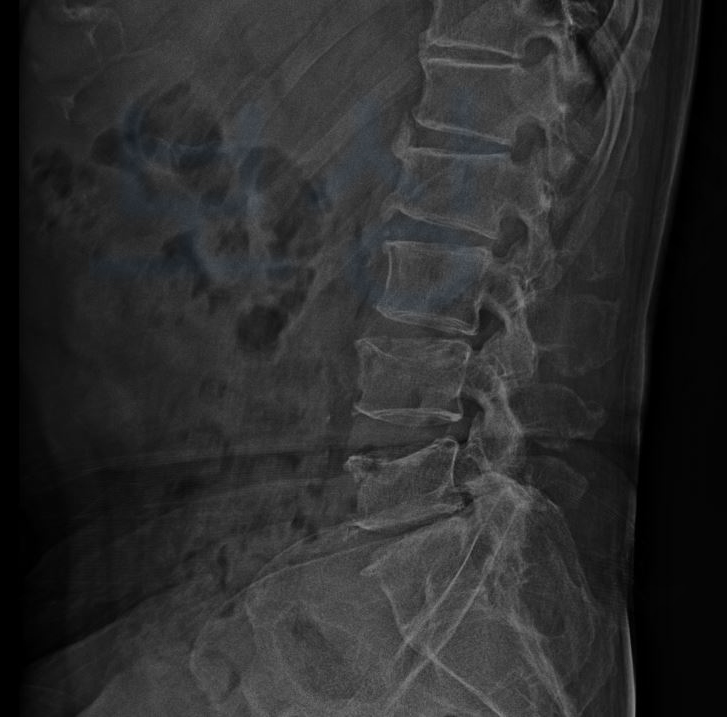

그 결과,

L4 부위의 골절 / L5 부위의 골절

진단을 받으셨습니다. L 은 Lumbar의 약자로서 4번, 5번은 척추체의 숫자를 의미합니다.

image

위 사진을 보시는 것처럼 요추 4번 5번이 압박골절되어 척추체의 전면이 주저앉은 모습 보이시죠? 요추 4번 5번 압박골절로 곽@@님은 TLSO 보조기를 착용하며 최소 12주간 입원 및 요양을 하셔야 했죠.